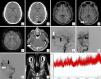

A 36-year-old male presented to the Emergency Department with clinical symptoms of blurred vision of progressive onset of two years of evolution. The ophthalmological examination revealed the existence of bilateral papilledema. Using cranial computed tomography and magnetic resonance imaging, the presence of a right occipital pial arteriovenous malformation was certified. Arteriographically, pial arterial contributions dependent on the right middle cerebral artery and the right posterior cerebral artery were identified. Venous drainage was located at the level of the superior sagittal sinus. An associated right transverse sinus stenosis was also identified. The existence of secondary intracranial hypertension was corroborated by monitoring with an intracranial pressure sensor. An interventional procedure was carried out consisting of embolization of the arterial supplies of the lesion using Onyx®. The clinical-radiological findings after the procedure were favorable: the papilledema disappeared and complete exclusion of the malformation was achieved. A new intracranial pressure measurement showed resolution of intracranial hypertension. Subsequent regulated radiological controls showed complete exclusion of the malformation up to 5 years later.